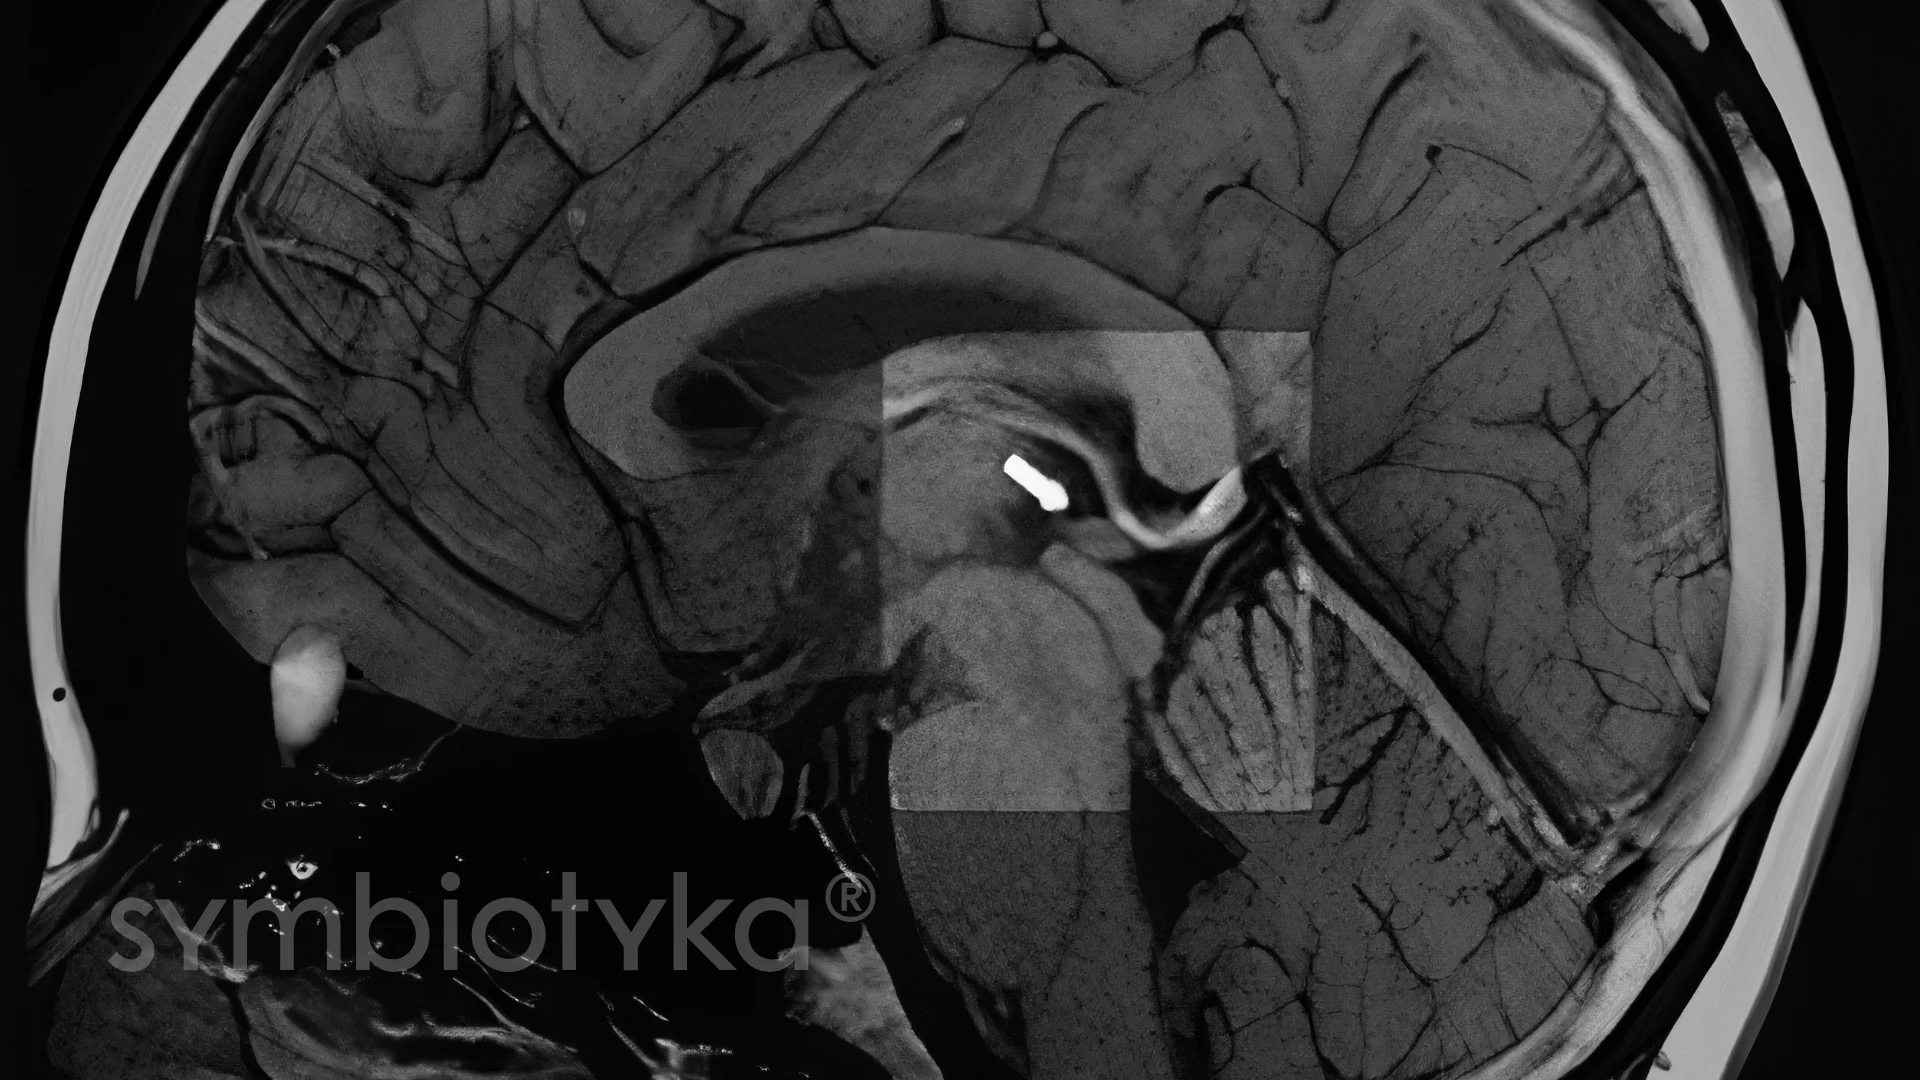

Діагностика кальцифікації епіфіза ґрунтується на інструментальних методах, які дозволяють візуалізувати структуру шишкоподібної залози та оцінити ступінь мінералізації. Додаткові аналізи використовують для виявлення функціональних порушень або виключення супутніх патологій центральної нервової та ендокринної систем. Оскільки кальцифікація може бути як віковою нормою, так і проявом інших процесів, важливо поєднувати дані візуалізації з клінічною оцінкою.

Комп’ютерна томографія (КТ) та магнітно-резонансна томографія (МРТ) — основні методи, які дають змогу виявити кальцифікати в області епіфіза.

Залежно від ситуації лікар може призначити один або обидва методи для повної картини.